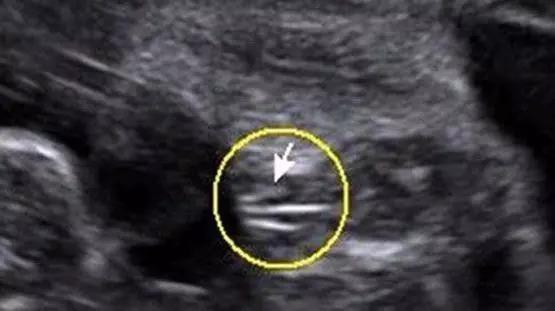

最明显的男宝宝彩超图

最明显的男宝宝彩超图,男宝四维小鸡图片大全

男宝四维小鸡图片大全

3个亮点是男孩彩超图

男宝宝彩超图片

男宝彩超图片